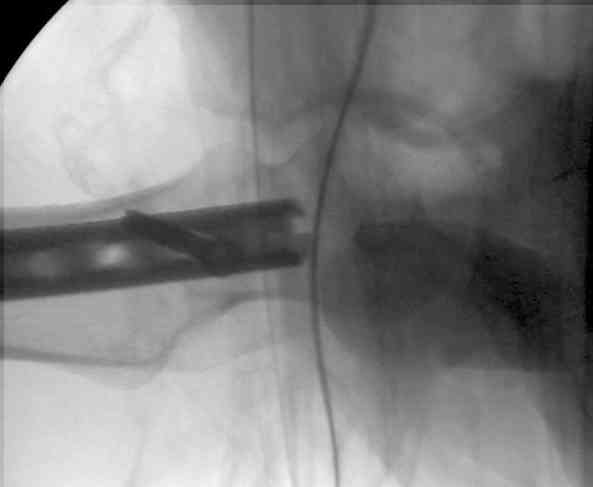

Вот несколько. С тисками и трубой на днях сделаем.

> Вот несколько. С тисками и трубой на днях сделаем.

Саша, последний штифт, пожалуй, перегнули?

> Саша, последний штифт, пожалуй перегнули?

Там заход сделан как для прямого штифта, не через вертел.

И правда, не через вертел. Тогда зачем гнули?